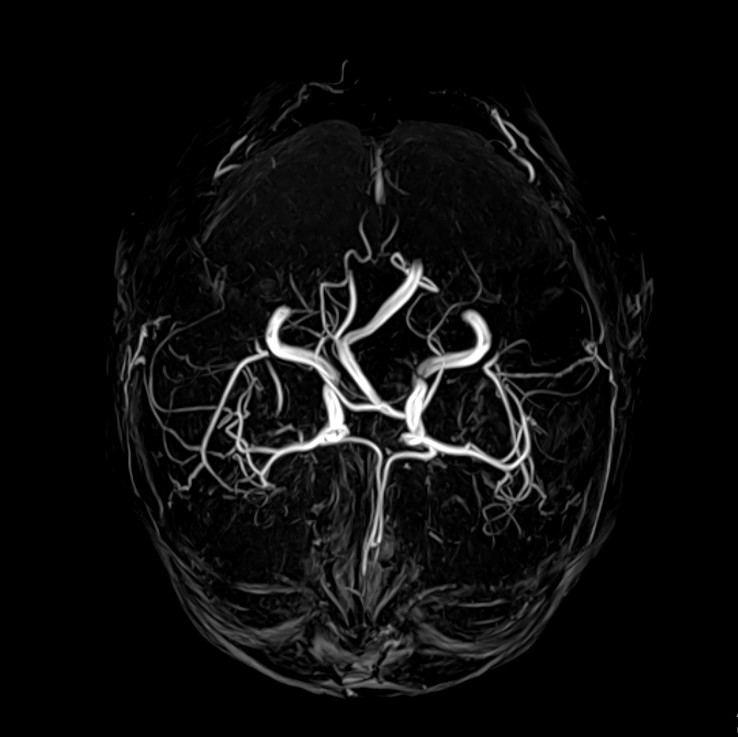

МРТ сосудов, в отличие от КТ, является наиболее безопасным исследованием и не сопровождается лучевой нагрузкой, и зачастую нет необходимости вводить контрастные вещества для повышения визуализации. В этой связи, МР-ангиографию можно делать пациентам с сопутствующими патологиями, беременным и детям необходимое количество раз. Также, немало важной особенностью МРТ является возможность оценки не только самих сосудов, но и их взаимодействия с тканями головного мозга. Стоит отметить, для МРТ характерна определенная область исследования и время, затрачиваемое на исследование, составляет 10-15 минут.

В клинической практике МР-ангиография является скрининговым методом и только лишь при выявлении каких-либо патологических изменений в сосудах или близлежащих тканях назначают КТ-ангиографию, которая позволяет более детально изучить найденную патологию. УЗ метод является дополнительным и помогает оценить состояние кровотока.